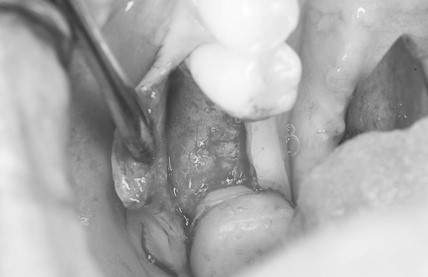

口腔内写真

- Befor

- After

| 年齢 | 50代・男性 |

| 主訴 | 部位:左下6番7番 主訴:左下奥歯腫れて痛い。 |

| 治療内容 | 左下6番抜歯、左下6番7番骨造成、インプラント埋入 |

| 治療費 | 合計:1,232,000円 ・内訳 診断料:55,000円 サージカルガイド2本:66,000円 GBR:110,000円×2本 埋入料:165,000円×2本 静脈内鎮静麻酔:77,000円 2次OPE:22,000円×2本 仮歯:55,000円×2本 上部構造(フルジルコニア):165,000円×2本 (2023年1月現在) |

| 治療期間 | 約8ヶ月 |

| 治療方針 | 元々支台歯に負荷がかかりやすいとされている延長ブリッジを抜歯し、1本単体でしっかりかめるようにインプラントを2本埋入した。骨吸収も進んでいたため、※GBR法で骨造成を同時に行った。 治療と並行して、全顎的な歯周病治療も行い、今後は歯周病が進行しないよう、こまめにメンテナンスに通っていただく。 |

| 担当者所見 | 6番は歯根分割された被せ物が7番の欠損部との延長ブリッジとされており、強い咬合と歯周病も相まって負荷がかかり動揺し、歯として機能しなくなったため、抜歯となった。 |